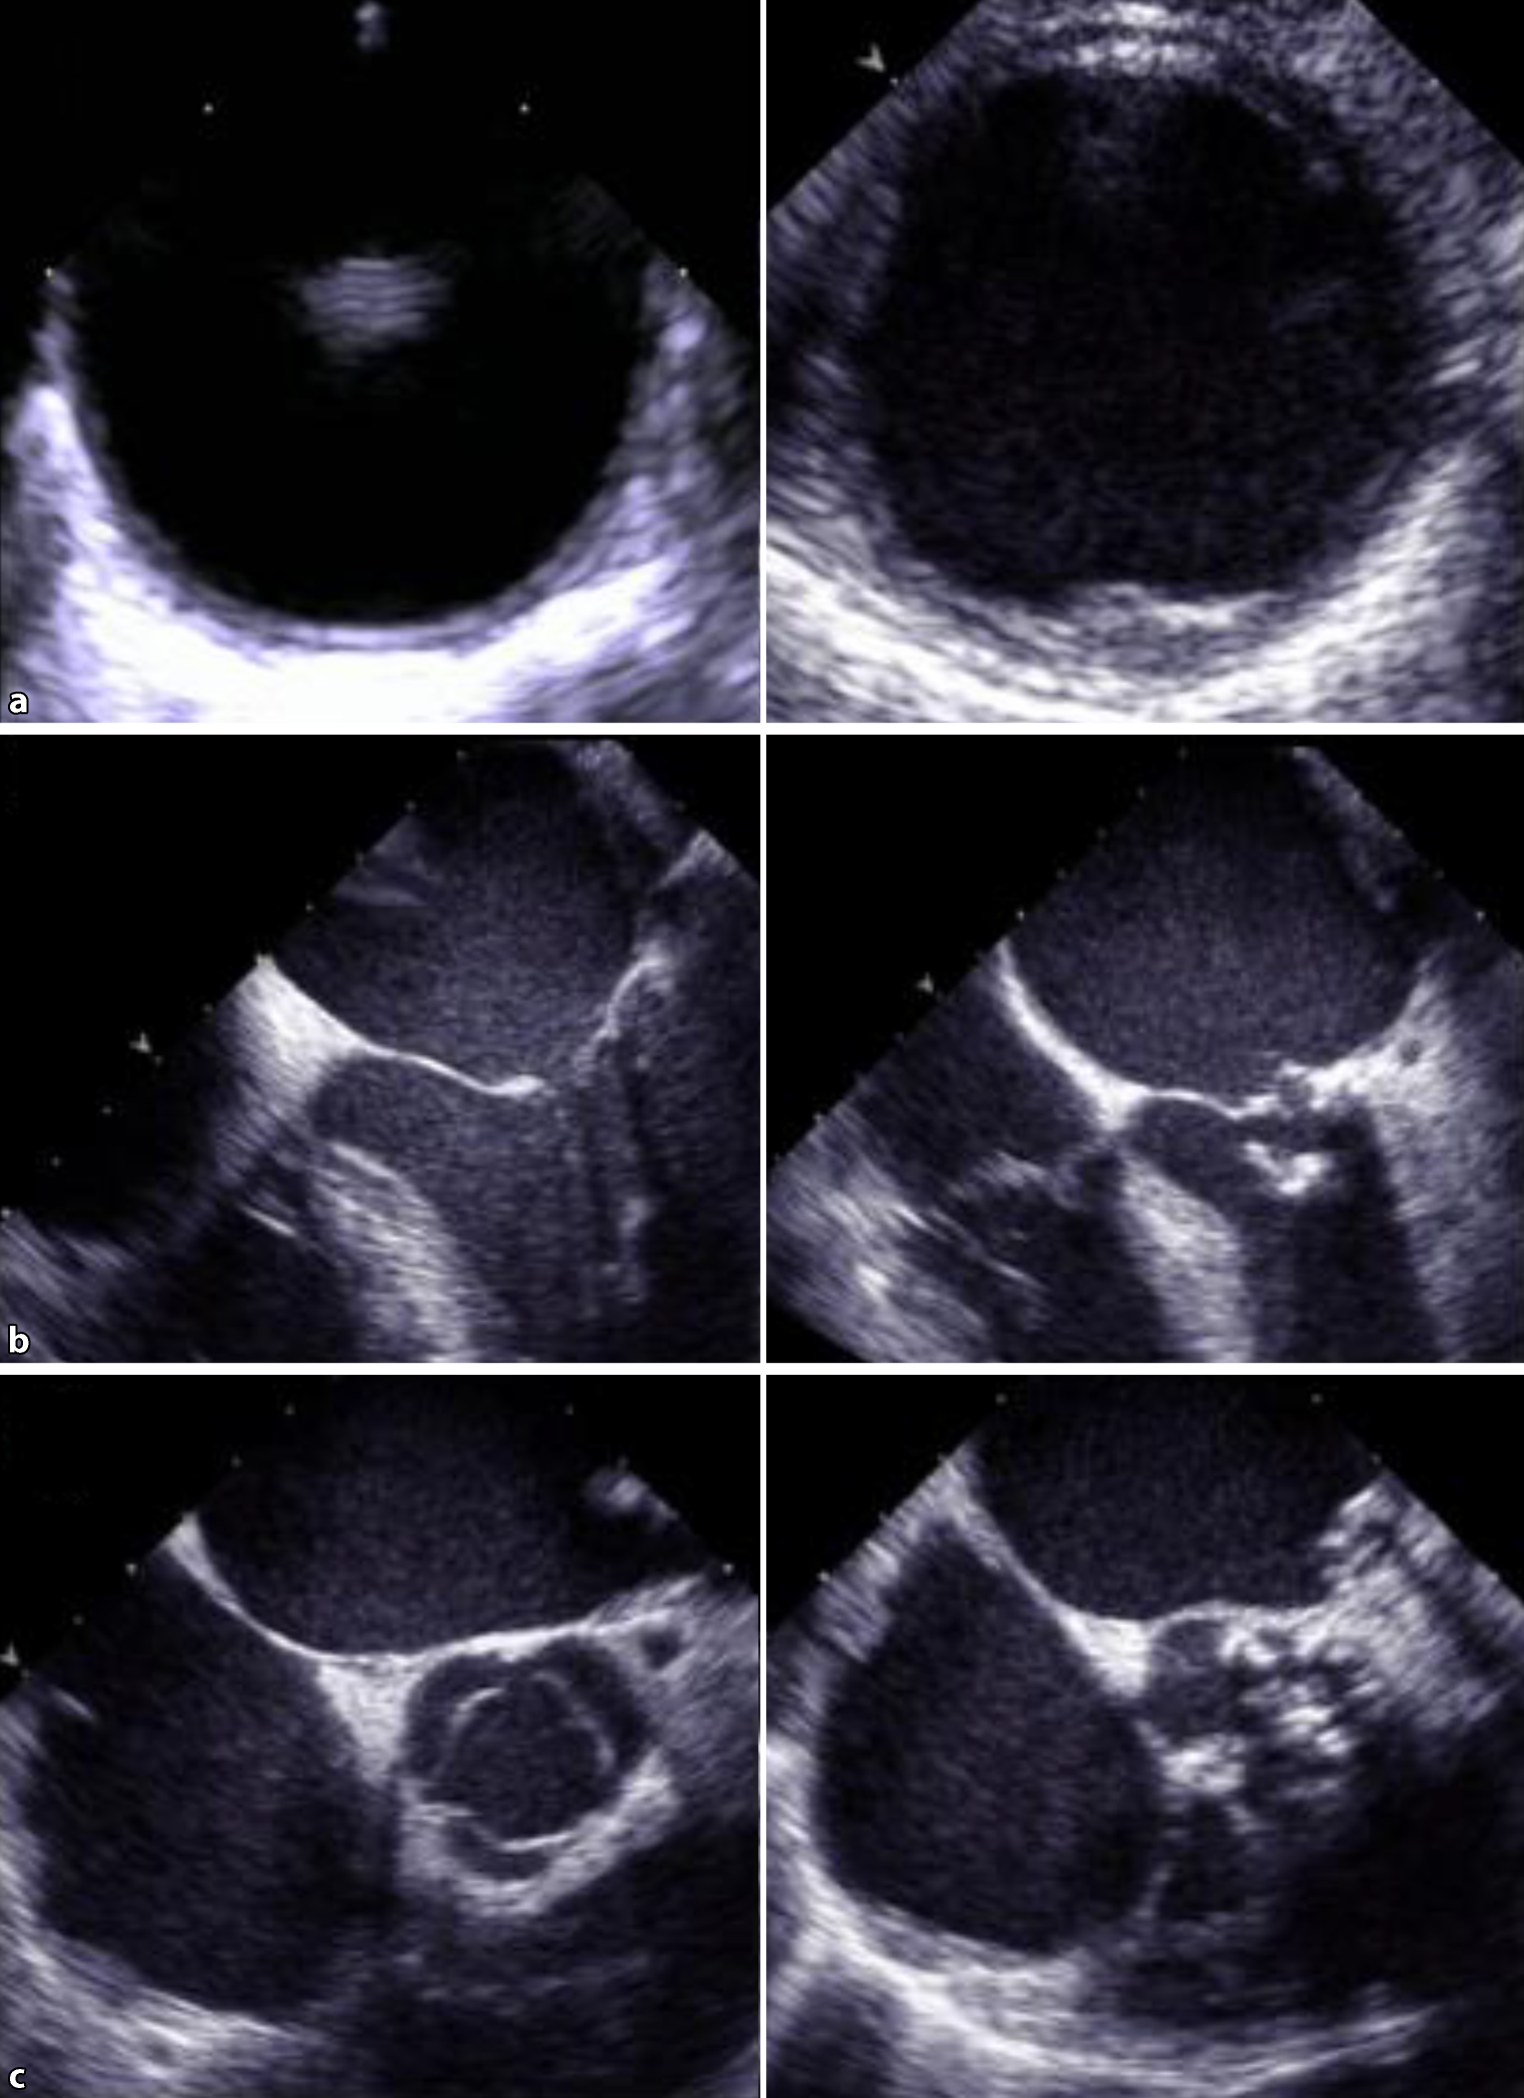

The degree of calcification is reported as no plaque, minimal plaque, minimal to moderate plaque, moderate plaque, moderate to severe plaque, and severe plaque. The differentiation between the groups is made by visual quantification only. To minimize interobserver variability and to reliably identify those patients with relevant aortic plaque, we evaluated two groups, one with minimal or no aortic plaque and one with more than minimal aortic plaque. Presence of MAC was diagnosed by visual assessment and defined as the presence of at least mild calcification of the mitral annulus. We evaluated two groups, one without MAC and one with at least mild MAC. Presence of aortic stenosis (AS) was diagnosed by visual assessment as well as by interpretation of continuous wave Doppler measurements. We evaluated two groups, one without AS and one with at least mild AS (Fig. 1).

Representative images displaying a transesophageal short axis view of the descending thoracic aorta (panel a) without (left side) and with (right side) aortic plaque, a transesophageal four-chamber view (panel b) with normal (left side) and severely calcified (right side) mitral valve, and a transesophageal short axis view of the aortic valve (panel c) with normal (left side) and severely calcified (right side) morphology